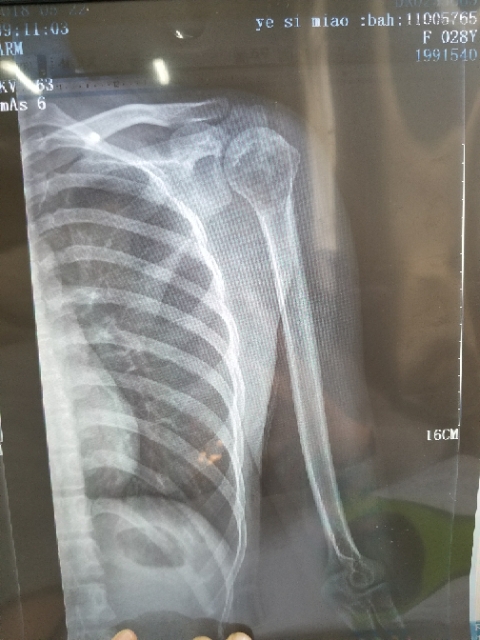

X-man 02019-01-22 患者本人十九岁,九月十号因恶性骨肉瘤在云南省肿瘤医院做了截肢手术,后发现肺上有三个结节,一个大约一厘米,两个不足一厘米,请问...